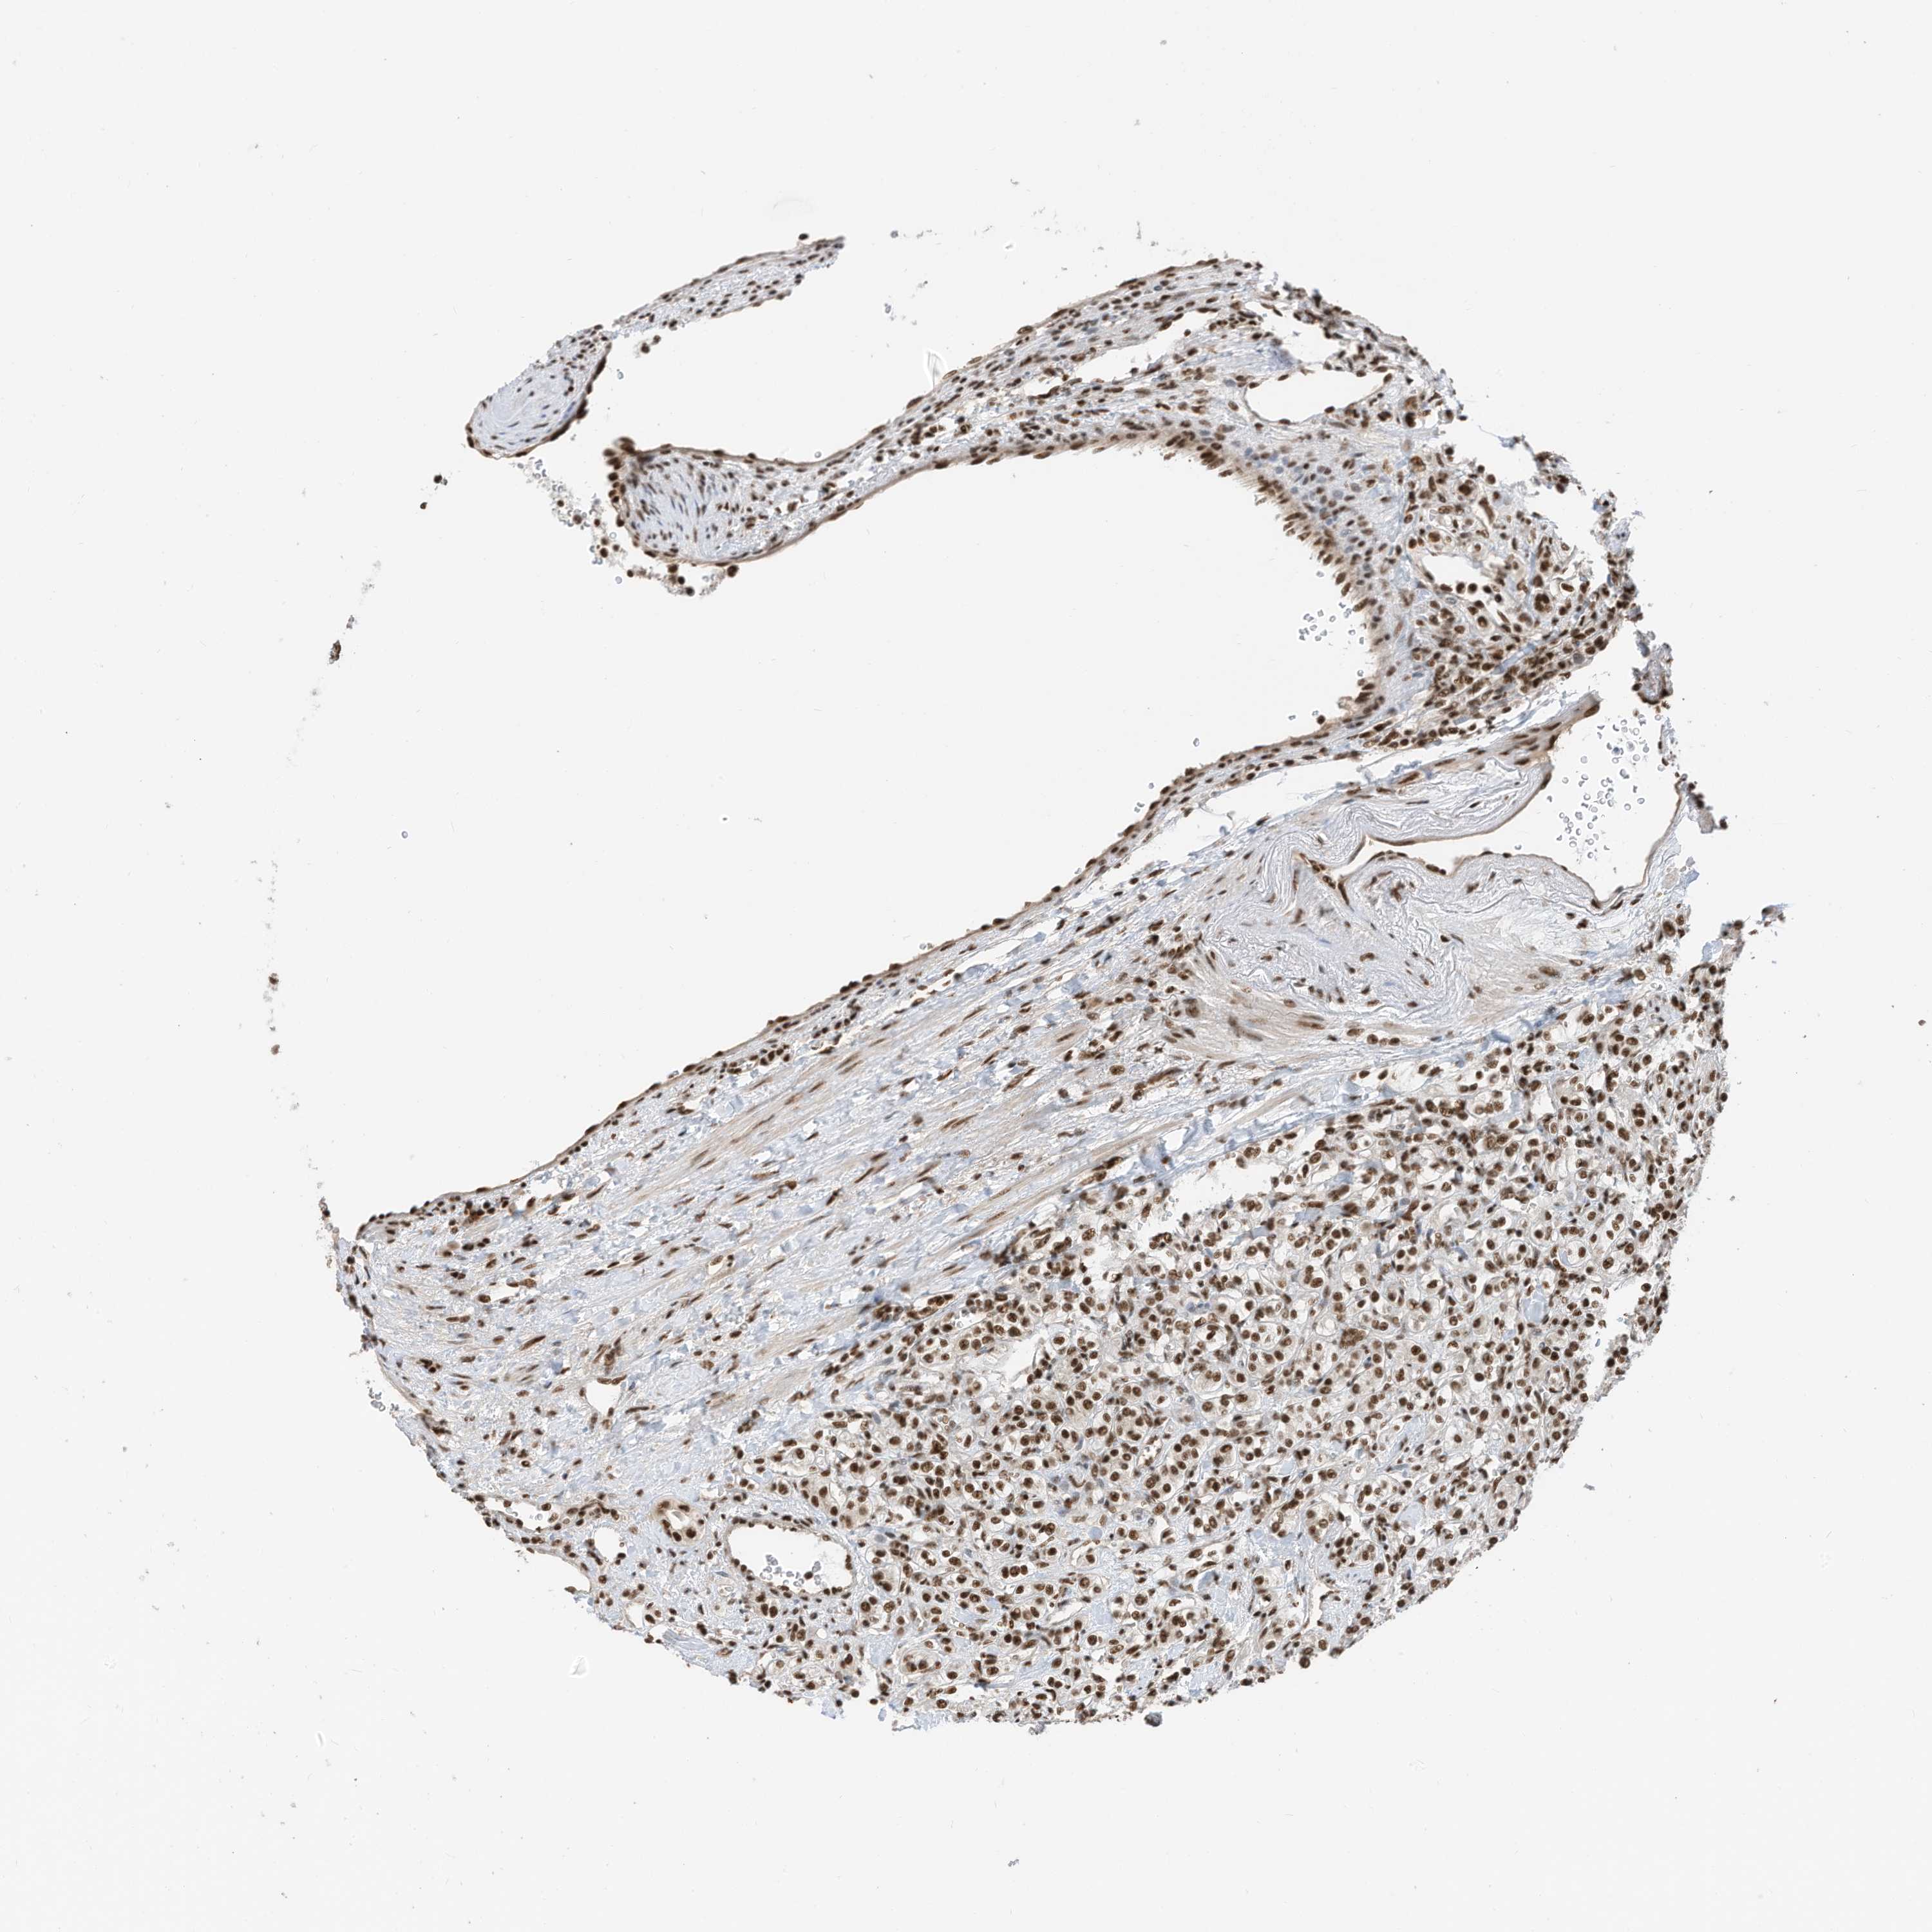

CANCER RENAL CANCER Show tissue menu

KICH TCGA KIRC TCGA KIRC VALIDATION KIRP TCGA PROTEIN RCC CPTAC PROTEIN EXPRESSION